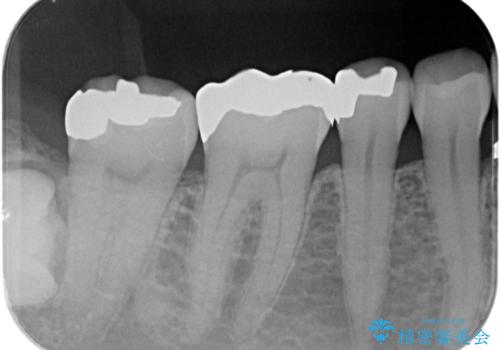

- 詰め物が外れたから作り直しをしたいとのことで来院されました。

外れた状態で日にちが経過していたため、まわりの歯ぐきが歯の上に乗っかっている状態です。

- 右下7 ゴールドインレー 77,000円費用は治療当時の料金となります

歯ぐきの形を整えることで精度の良い詰め物を入れることができました。